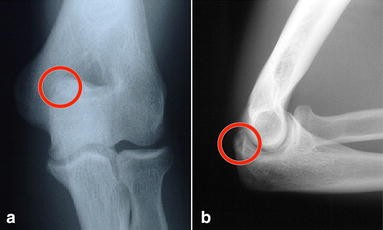

Olecranon impingement within the olecranon fossa. In addition any activity that causes increased valgus stress on the elbow can also cause posterior impingement syndrome or. Posterior Impingement of the Elbow Fig.

Posteromedial Elbow Tests Posteromedial Impingement Test Elbow at 20º to 30º Valgus Stress Force Terminal Extension. Elbow impingement is a condition characterized by compression and damage to soft tissue such as cartilage situated at the back of or within the elbow joint. May stimulate the formation of osteophytes with chronic impingement.